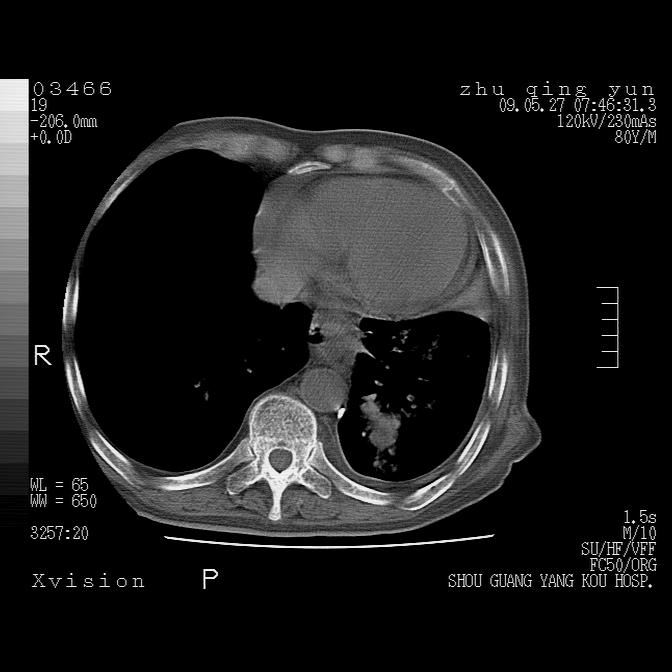

病人男性,年龄80,气喘来院,其他病史不太详细,1月前有过恶心,呕吐,在当地人民医院做过钡餐,诊断胃炎,

1)考虑左肺中央型肺癌并阻塞性肺炎,后下纵隔受侵伴纵隔淋巴结转移。2)双侧少量胸腔积液,胸膜增厚。3)心包积液。

左肺下叶见多发片状及结节状病灶,左肺基底段支气管闭塞,纵隔内见多发淋巴结肿大,纵隔向左侧移位,左侧胸廓变小。应该是左肺下叶中心型肺癌,纵隔淋巴结转移,左侧肺内转移,左肺基底段肺不张,阻塞性肺炎。

1)考虑左肺中央型肺癌并左肺下叶阻塞性肺炎、不张;左胸膜腔积液、心包积液、纵隔淋巴结转移;癌肿累及左心房。2)左心室大。冠状动脉壁钙化斑。

恶性占位是肯定的,并累及心包并纵隔淋巴结转移/左肺癌性淋巴管炎/肺部感染。是中心性或纵隔型肺癌,还是后纵隔恶性占位,还是食道中下段癌或食道受累需鉴别。

支持以上,左肺肿块应该是周围型吧,考虑左下肺周围型肺癌伴肺内转移,阻塞性肺炎,纵隔淋巴转移,左侧胸膜及心包转移